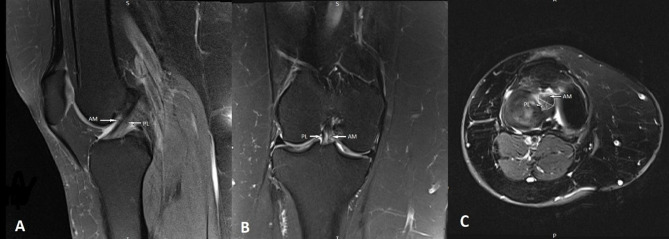

The Anterior Cruciate Ligament (ACL) is considered the most commonly injured ligament of the knee. Magnetic Resonance Imaging (MRI) has become an indispensable imaging tool and modality of choice for assessing and managing knee conditions. This article outlines an effective MRI imaging technique that improves the diagnostic accuracy of ACL injuries of the knee, covering the appropriate pulse sequences and optimal imaging planes. Furthermore, the article provides a comprehensive review of the appearance of complete and partial ACL tears on MRI in the acute and chronic phases. In addition, it identifies and illustrates the primary MRI signs (signs related to the absence or abnormal visualization of the ACL fibers) and secondary MRI signs (signs related to the mechanism of injury or associated knee injuries) of ACL injury.